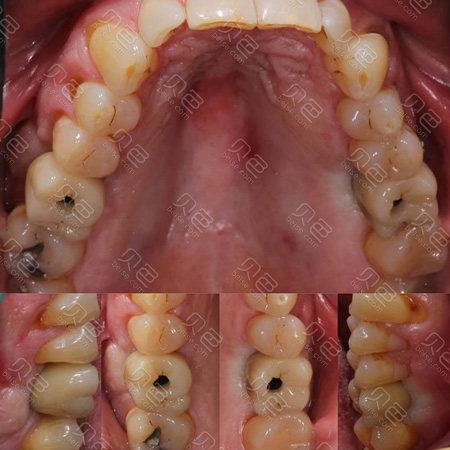

高牙冠的风险与处理

风险:牙冠高度超过10mm(后牙)或12mm(前牙)时,易出现咬合早接触,导致种植体承受过大侧向力,长期可能引发种植体松动、骨吸收;高牙冠的“悬臂效应”会增加牙冠折裂风险,尤其当咬合集中在牙冠远中时,高牙冠与牙龈间易形成台阶,堆积菌斑,诱发种植体周围炎。

处理:若术后发现牙冠过高,需通过咬合纸标记早接触点,精确调改咬合面,消除侧向力;若高度差异过大,需拆除牙冠,重新取模制作合适高度的牙冠;对于已出现骨吸收的患者,需结合骨增量手术调整修复方案。